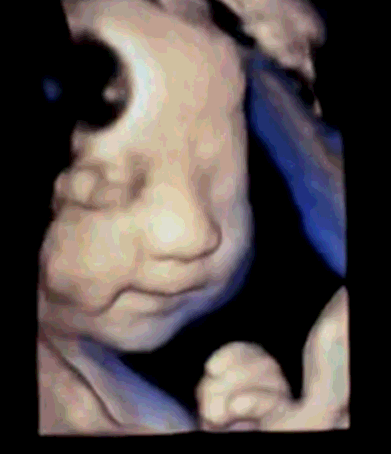

四维彩超的全称为四维彩色超声诊断仪,是目前世界上最先进的彩色超声设备。四维彩超的诊断资料有利于医生检测出各种异常,对于胎儿的成长发育做出准确的判断。那么四维彩超上的数据具体应该怎么看,美琳达妇儿医院四维彩超医生陈月芳和您说一说关于四维彩超的那些事儿!

感受、聆听已经无法满足我们对胎宝宝的爱,只有“清晰地看见”才能让我们欣喜若狂……